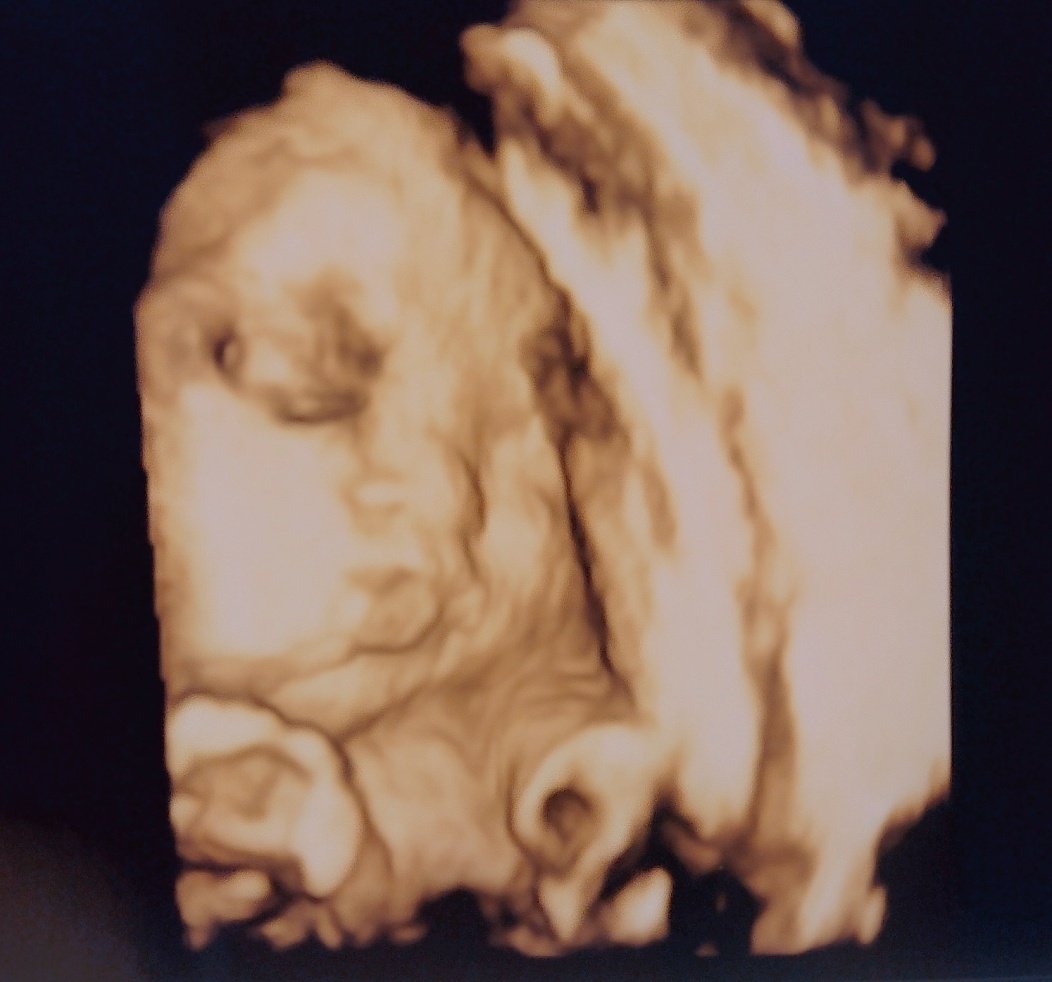

19週0日目 ゆるい妊娠記録 1時間前 ※予告なくエコー写真が出てきます病院行ってきました〜今日から19週😭来週で妊娠6ヶ月! 早いです低体重早産で生まれてきて救命が行われる境目が22週らしいですねあと少しで流産の可能性がこれまた低くなる😮💨 赤ちゃんの3dエコー写真のメリットは? 3dエコー写真のメリットはなんといっても、 顔の表情や仕草が立体的にわかる こと!! エコー写真アルバム 「10ツキ10カものがたり」 かわいい絵本のようになっていて、エコー写真が6枚入ります。 (切って貼れば、もう少し入れられます^^) こんな感じ↑で、エコー写真を貼って、 上から保護フィルムを貼り合わせることで、エコー写真の

でも4dエコーしてもらった時は 鼻がでかすぎて 、えっ?ってビックリしちゃいました。笑 エコー写真がどれくらい正確なのか産まれた息子と比較してみたいと思います! 21週3日の4dエコー これは初めて4dエコーをした時の写真です。妊婦健診毎に増える"エコー写真"、時間が経つと色あせてしまいます。 無料アプリ"フォトスキャンby google フォト"を使用するとカメラ初心者でも簡単にエコー写真をデータ化できます。 まだエコー写真を整理していない妊婦の皆さんお試しください。 可愛い? 怖い? 妄想力が試されるエコー写真_トーキョー爆誕子育生活 検診に行くと必ず超音波検診で胎児の様子を確認しますが、その際にもらえるのがエコー写真。 白黒で胎内の様子を撮したもので、お子さんをお持ちのパパママであればお馴染みだ